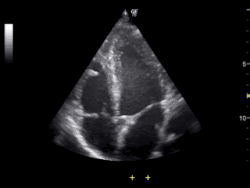

Ultrasound of human heart showing the four chambers and mitral and tricuspid valves

Echocardiography is an essential tool in cardiology, assisting in evaluation of heart valve function, such as stenosis or insufficiency, strength of cardiac muscle contraction, and hypertrophy or dilatation of the main chambers. (ventricle and atrium)